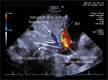

Introduction: Optimal positioning of double lumen bicaval canula for extracorporeal membrane oxygenation (ECMO) support used as a rescue measure in refractory hypoxaemia is essential to facilitate adequate oxygenation, prevent recirculation and avoid complications. Method: Echocardiography via transoesophageal or transthoracic windows can be used as guidance and as a surveillance technique to prevent cannula malposition. We describe a case of Double-Lumen Bicaval VV ECMO cannula malposition leading to a massive retrograde hepatic venous flow. Conclusion: Rapid echocardiographic diagnosis was pivotal in preventing potentially fatal complications.